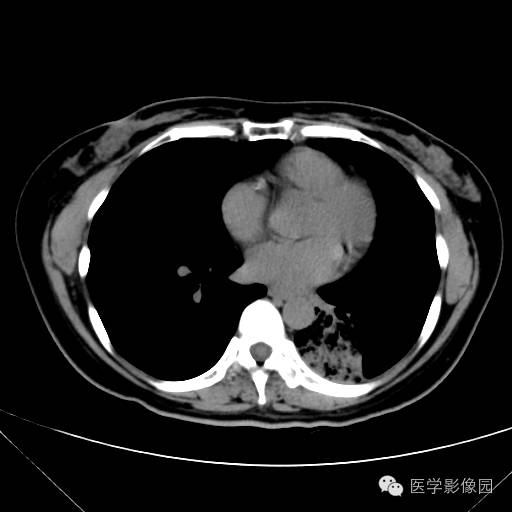

肺叶实变性支气管肺泡癌1例CT影像表现

【病例】肺叶实变性支气管肺泡癌1例CT影像表现